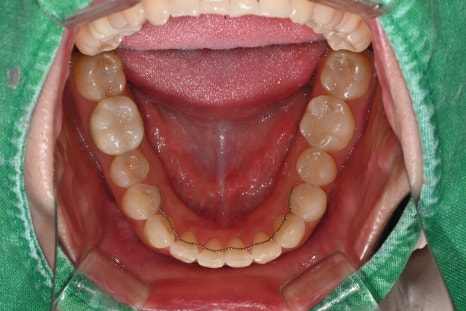

치료 전, 후 비교

<BEFORE>

<AFTER>

초진 시 파노라마와 구강 사진을 촬영해

전체 치아 상태를 확인했고,

특히 앞니 라인의 색·투명도·대칭이

전체적인 인상을 좌우하고 있어

라미네이트와 전치부 크라운을 조합한

설계가 가장 적합하다고 판단했습니다.